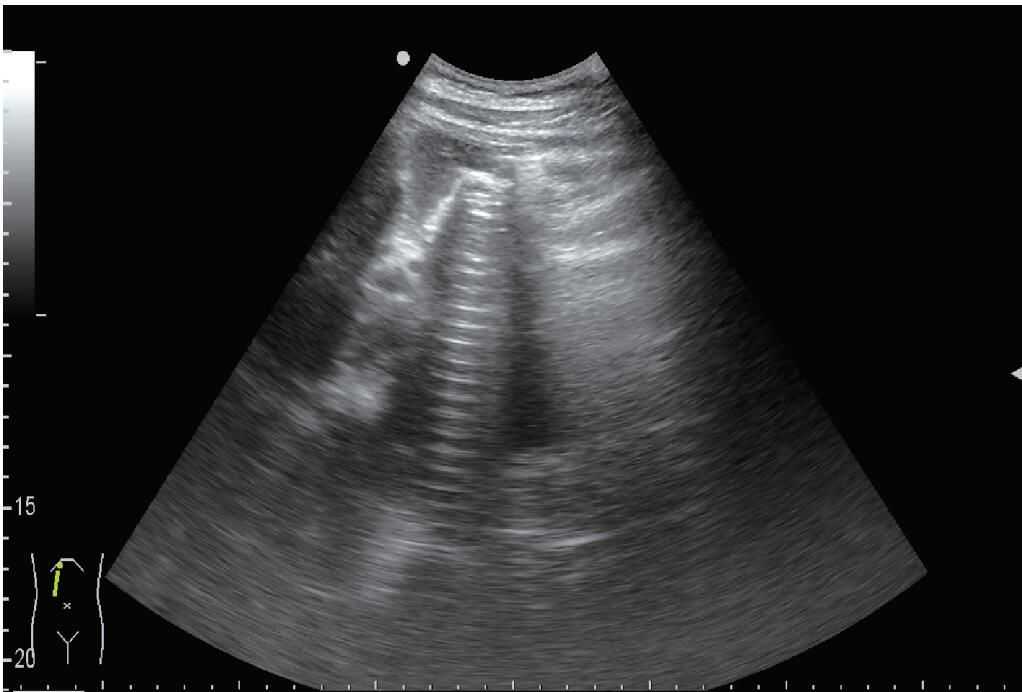

2.B模式利用显示器的灰阶显示声束扫描身体切面各个点的回波信号的振幅,最终形成二维图像,是超声诊断中最常用的模式(图1)。

图1B模式